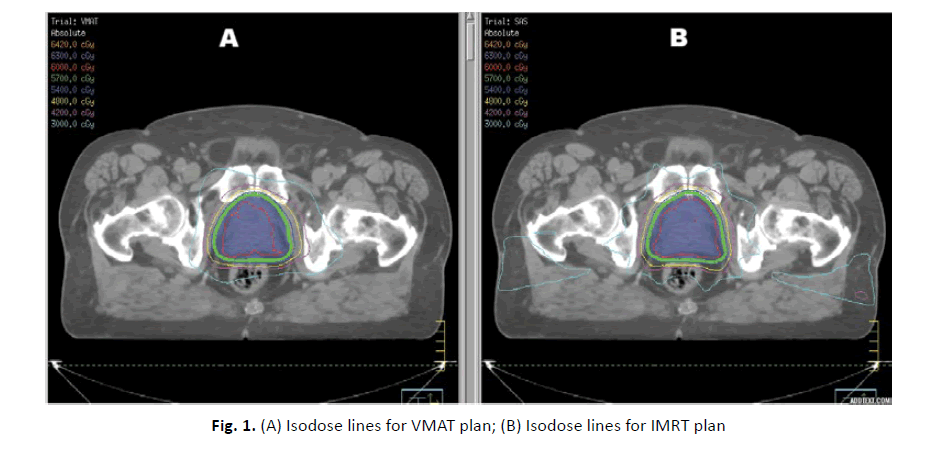

All plans were optimized using same planning constraints. Meeting OARs constrains was prioritized over target coverage at time of planning using both techniques. The DVH records were analysed, all VMAT plans were meeting the objectives required for hypofractionated radiation approach. Conversely, four IMRT plans did not meet the prerequisite parameters. VMAT was superior in terms of target volume coverage and OAR sparing (Figure 1).

Figure 1: (A) Isodose lines for VMAT plan; (B) Isodose lines for IMRT plan